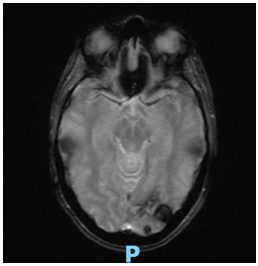

Posteriormente se solicita interconsulta al Servicio de Oncología y se realiza RMN de cerebro (Imagen 3) descartándose secundarismo en este órgano (se informó área de aspecto secuelar con depósitos de hemosiderina en secuencia de gradiente a nivel de la corteza occipital izquierda. La misma no presenta áreas de restricción o realces tras la administración de contraste ev.)

Imagen 3. RMN de cerebro al diagnóstico